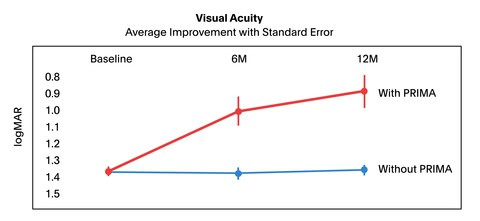

การทดลองดังกล่าวได้รับสมัครผู้เข้าร่วม 38 ราย โดยผู้เข้าร่วมการทดลองจะมีอายุ 60 ปีขึ้นไป มาจากในสหราชอาณาจักรและยุโรป แต่มีผู้เข้าร่วม 6 รายถอนตัวออกไปก่อนศึกษาครบ 1 ปี เพื่อวัดการพัฒนาด้านความคมชัดของการมองเห็น นักวิจัยใช้แผนภูมิสายตาแบบคลาสสิกในการวัด โดยอาสาสมัครเริ่มต้นด้วยความคมชัดของการมองเห็นโดยเฉลี่ยที่ 20/450 ขณะที่ความคมชัดของการมองเห็นปกติถือว่าอยู่ที่ 20/20 ซึ่งในสหรัฐอเมริกา สายตาที่จัดว่าบอดตามกฎหมายจะอยู่ที่ 20/200 หรือแย่กว่านั้น

หลังจากผ่านไป 1 ปี ผู้เข้าร่วมการทดลองจำนวน 32 คนสามารถอ่านแผนภูมิการมองเห็นได้เพิ่มขึ้นเกือบ 5 บรรทัด หรือ 23 ตัวอักษร เมื่อเทียบกับช่วงเริ่มต้นการศึกษา ซึ่งเพียงพอที่จะทำให้สายตาของพวกเขาดีขึ้นเป็น 20/160 โดยเฉลี่ย Daniel Palanker กล่าวว่า ผู้เข้าร่วมบางคนสามารถมองเห็นได้คมชัดถึง 20/63 โดยใช้คุณสมบัติซูมในตัวของอิมแพลนต์ แม้ว่าผู้เข้าร่วมส่วนใหญ่จะเห็นการปรับปรุงที่เห็นได้ชัดหลังจากผ่านไป 1 ปี แต่ผู้เข้าร่วม 5 คนไม่มีพัฒนาการด้านการมองเห็น ซึ่งนับว่าเป็นผลลัพธ์ที่ได้นั้นน่าประทับใจมาก